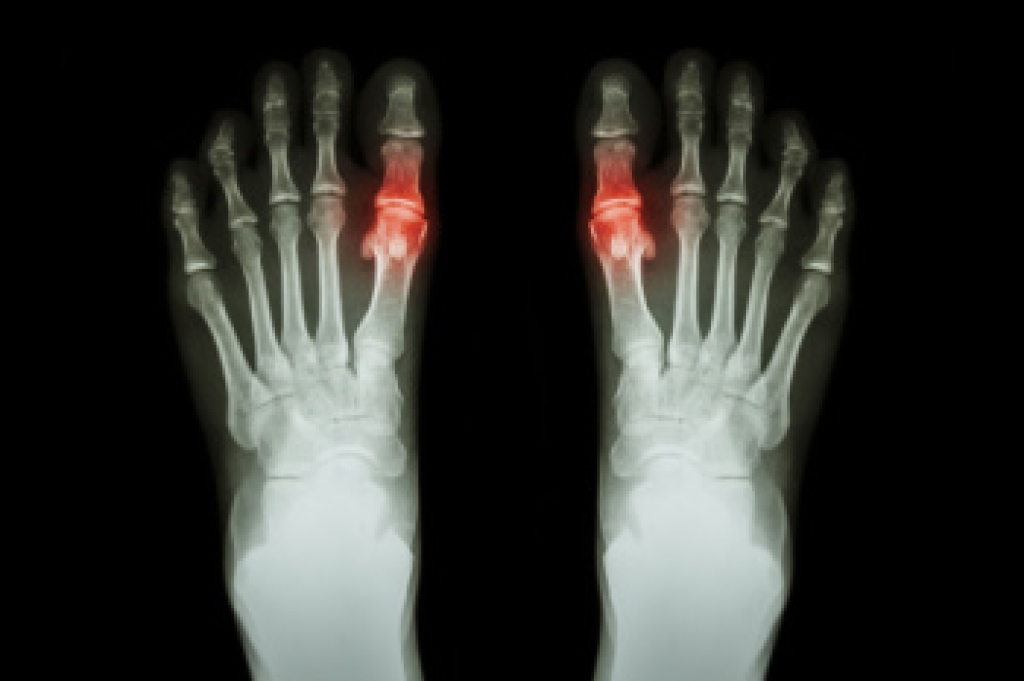

Dr. Kenneth Williams is a board-certified podiatrist with over three decades of experience. He is known to be thorough, and will always try to treat his patients conservatively. He has helped patients with all kinds of foot and ankle conditions, such as: foot pain, plantar fasciitis and other forms of heel pain, ingrown toenails, diabetic foot care and limb salvage, and more. As a highly skilled podiatric surgeon, Dr. Williams offers surgical solutions when necessary, such as advanced minimally invasive surgery (MIS) for the correction of painful bunions.